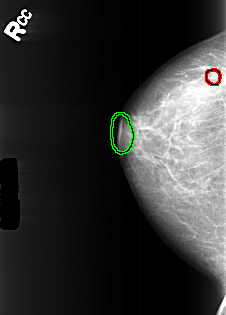

B_3445_1.RIGHT_CC

FILE: B_3445_1.RIGHT_CC.OVERLAY

TOTAL_ABNORMALITIES 2

ABNORMALITY 1

LESION_TYPE MASS SHAPE LYMPH_NODE MARGINS N/A

ASSESSMENT 2

SUBTLETY 3

PATHOLOGY BENIGN_WITHOUT_CALLBACK

TOTAL_OUTLINES 1

BOUNDARY

ABNORMALITY 2

TOTAL_OUTLINES 2